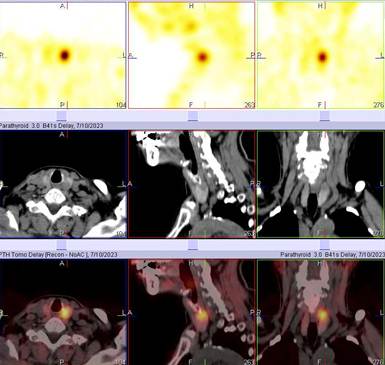

常用的顯像方法為99mTc-MIBI雙時(shí)相法。無(wú)需特殊準(zhǔn)備,盡量停用維生素D和鈣劑2周,檢查前無(wú)需禁食水。靜脈注射99mTc-MIBI后,于15分鐘和120分鐘采集早期和延遲顯像。為了更精確的定位及識(shí)別多發(fā)病灶,需要增加斷層融合顯像(SPECT/CT)。

病例1:女68歲,半年前無(wú)明顯誘因出現(xiàn)乏力納差癥狀,同時(shí)體重減少約15公斤,檢查發(fā)現(xiàn)血鈣:2.96 mmol/l(2.11-2.52mmol/l),PTH 513 pg/ml(參考值0-6.40 pg/ml),甲狀旁腺平面及斷層融合顯像顯示:左側(cè)甲狀旁腺區(qū)病變伴異常放射性濃聚,考慮功能亢進(jìn)甲狀旁腺病變。后行手術(shù)切除,病理證實(shí)為甲狀旁腺腺瘤。

病例2: 女52歲,無(wú)明顯誘因出現(xiàn)髖部疼痛,后查骨密度顯示重度骨質(zhì)疏松,給予“降鈣素+補(bǔ)鈣等”治療,癥狀好轉(zhuǎn)不明顯,再次就診查肌酐125 umol/L(參考值44-106 umol/L),鈣3.96 mmol/L(參考值2.11-2.52mmol/L),全段PTH: >2000.00pg/ml↑(參考值18.50-88.00 pg/ml)。甲狀旁腺平面及斷層融合顯像顯示:甲狀腺右葉下極后方占位伴放射性濃聚,考慮為功能亢進(jìn)的甲狀旁腺病變。手術(shù)切除,病理證實(shí)為甲狀旁腺腺瘤。

病例3:男,54歲,腎結(jié)石擬行碎石術(shù),發(fā)現(xiàn)血清鈣、PTH升高,血清磷減低,甲狀旁腺平面及斷層融合顯像顯示:甲狀腺左葉后下方低密度結(jié)節(jié)伴放射性濃聚,考慮功能亢進(jìn)的甲狀旁腺病變。后行手術(shù)治療,病理:甲狀旁腺腺瘤。